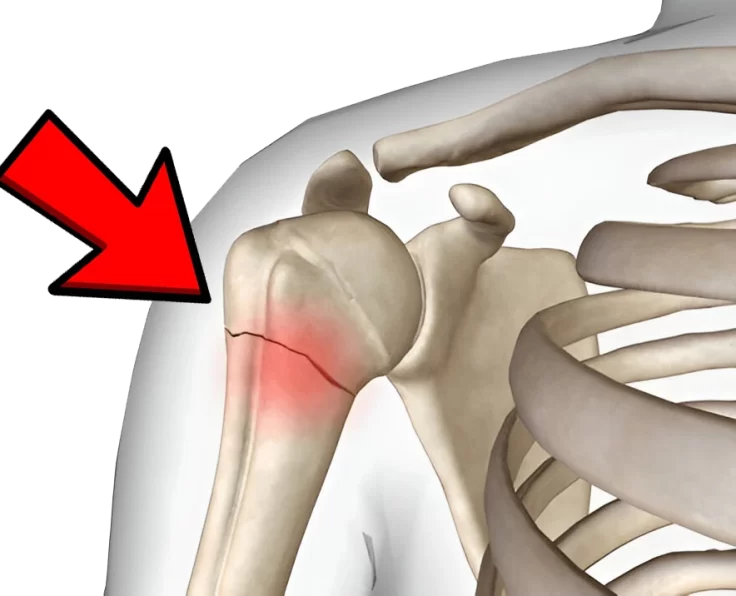

Proximal Humeral Fractures

Proximal humeral fractures are particularly common in the elderly. A few people have axillary nerve or artery injury (which reduces sensation across the middle deltoid).